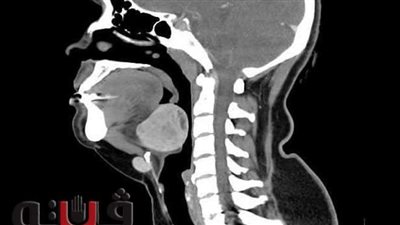

استئصال غدة درقية نادرة بالجزء الخلفي من اللسان لشابة بـ "طنطا الجامعي"

أعلن الدكتور محمود زكي، رئيس جامعة طنطا، نجاح فريق جراحي بقسم الأنف والأذن والحنجرة بمستشفى طنطا الجامعي من استئصال غدة درقية نادر وجودها بالجزء الخلفي من اللسان لشابة تبلغ من العمر 35 عاما في عملية نادرة استغرقت ساعتين.